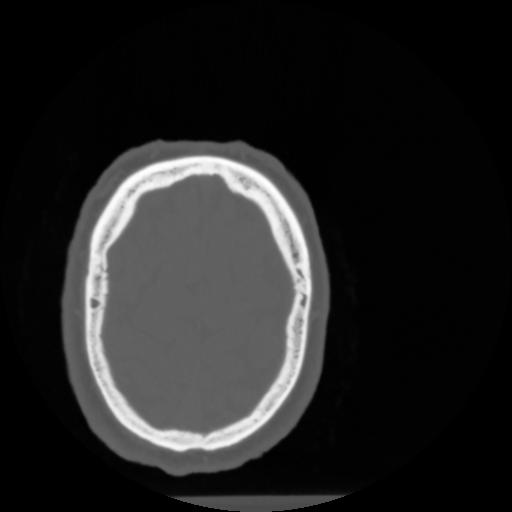

4 CEREBRO,,Vol,0.5,CEREBRO,,